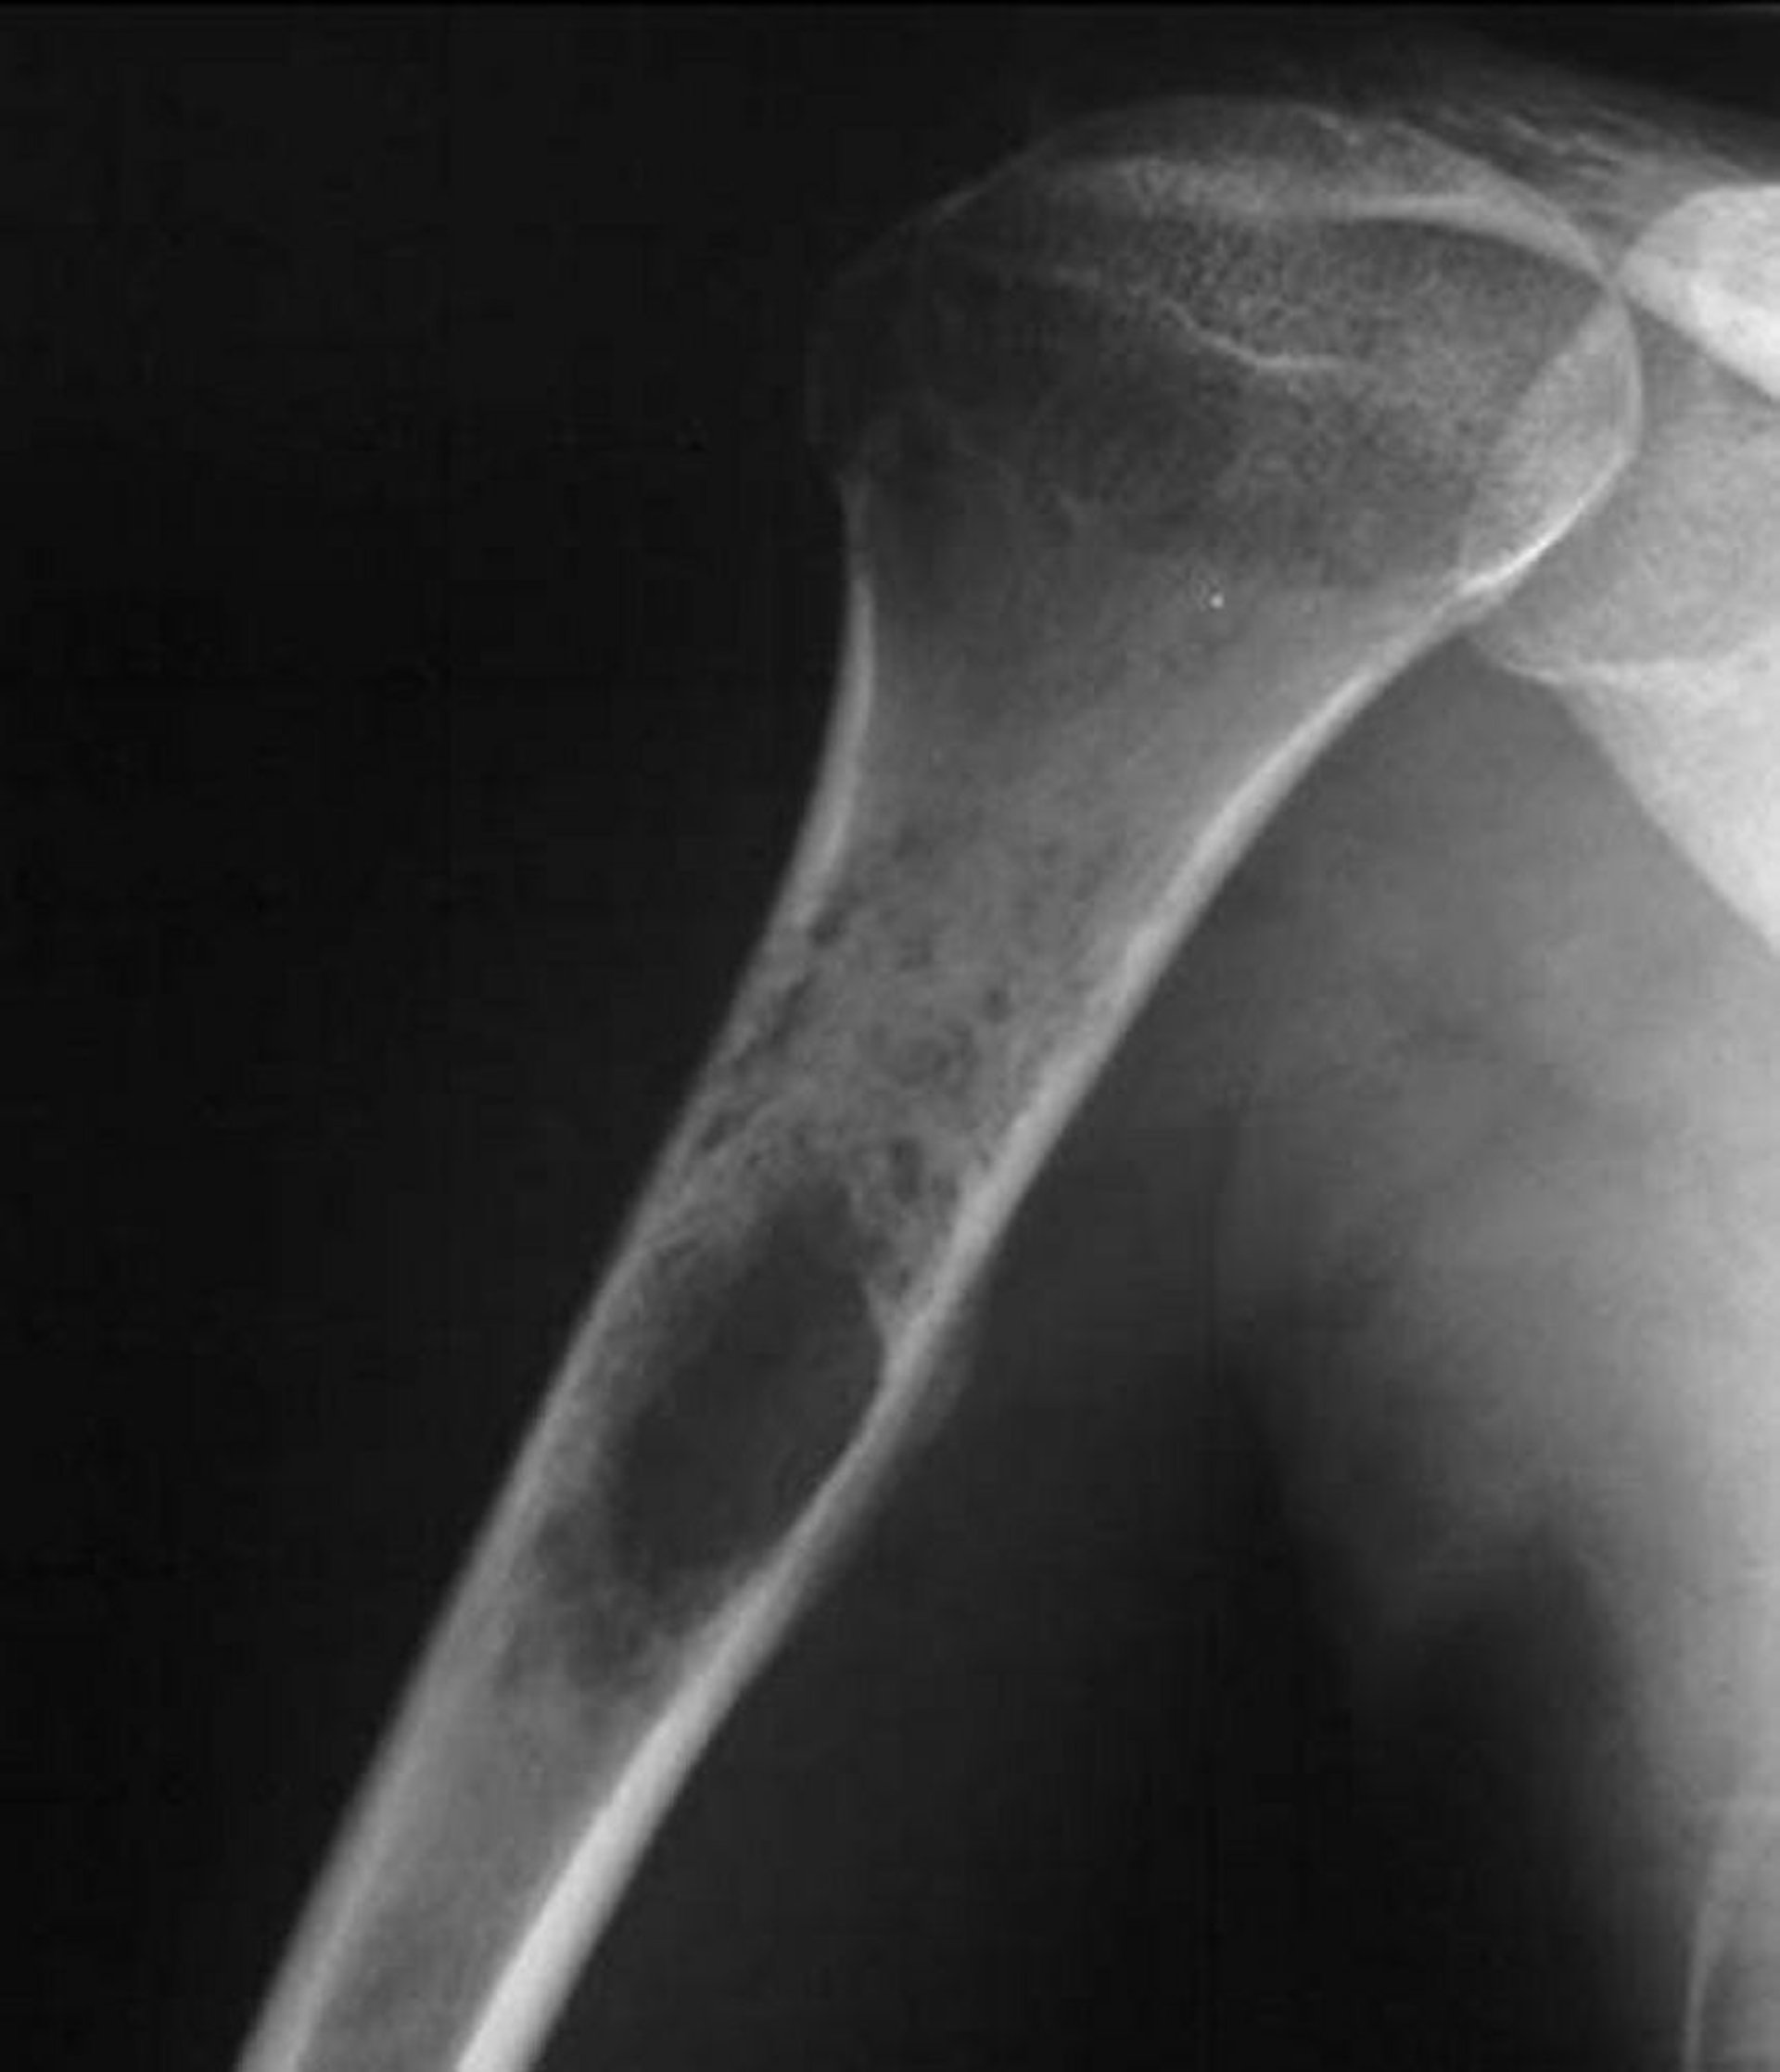

На данном рентгеновском снимке плеча показана пермеативная деструктивная опухоль, возникающая в проксимальном отделе плечевой кости, что характерно для саркомы Юинга.

Image courtesy of Michael J. Joyce, MD, and Hakan Ilaslan, MD.